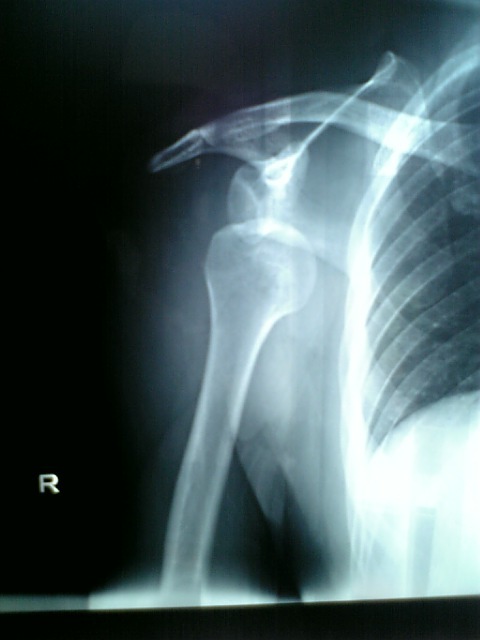

脱臼からもうすぐ2週間! |

写真を痛みに耐えながら記念に撮っておいたのが

あったのを思い出したので載せて見ました!

確実にあるべき所から下にずれてます・・・